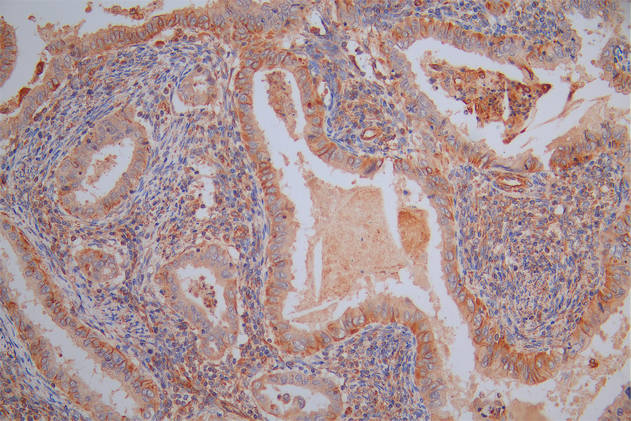

IHC image of CSB-RA555705A0HU diluted at 1:100 and staining in paraffin-embedded human skin tissue performed on a Leica BondTM system. After dewaxing and hydration, antigen retrieval was mediated by high pressure in a citrate buffer (pH 6.0). Section was blocked with 10% normal goat serum 30min at RT. Then primary antibody (1% BSA) was incubated at 4°C overnight. The primary is detected by a Goat anti-rabbit polymer IgG labeled by HRP and visualized using 0.05% DAB.